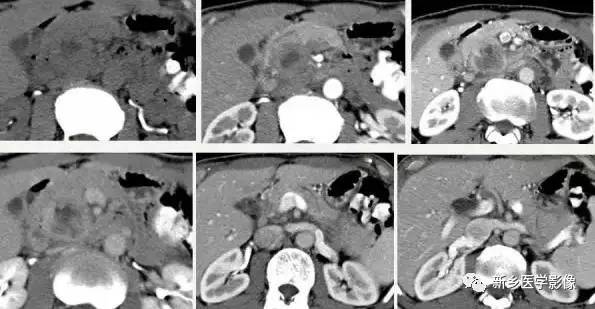

2.影像学诊断:CT 、M RI 上, 本病表现为胰腺边界清楚的大肿块, 囊实相间, 实性部分主要位于病变周边,有强化;囊性部分主要位于病灶中心区域, 囊变区密度较高, CT 值40 ~50Hu 。30 %的患者病变周边可见钙化。由于病变内常有出血,T1W I 上可见不均匀高信号, T 2WI 上见不均匀低信号 。M RCP 或E RCP 示胰管受压、移位或中断。 医学百科网 | YxBaike.Com